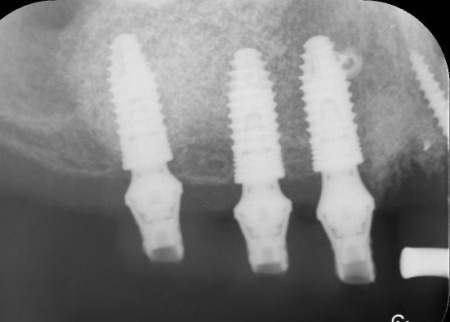

次に、右上奥歯と前歯にインプラント治療を行いました。

右上奥歯は、歯周病でインプラントを埋入するために必要な骨が不足していたため、上顎の奥にある上顎洞の底を押し上げて人工の骨を補う「サイナスリフト」という骨造成を併用しています。

右上前歯も同様に骨が少なかったため、こちらは骨の移植を行って骨量を確保したのち、インプラントを埋入しました。

インプラントが骨にしっかりとなじんだことを確認したら、白くて強度の高い人工歯「ジルコニアクラウン」を装着しました。

他院で治療を行った左下奥歯3本のインプラントは、土台をそのまま活かして人工歯だけ作り直し、噛み合わせを調整します。